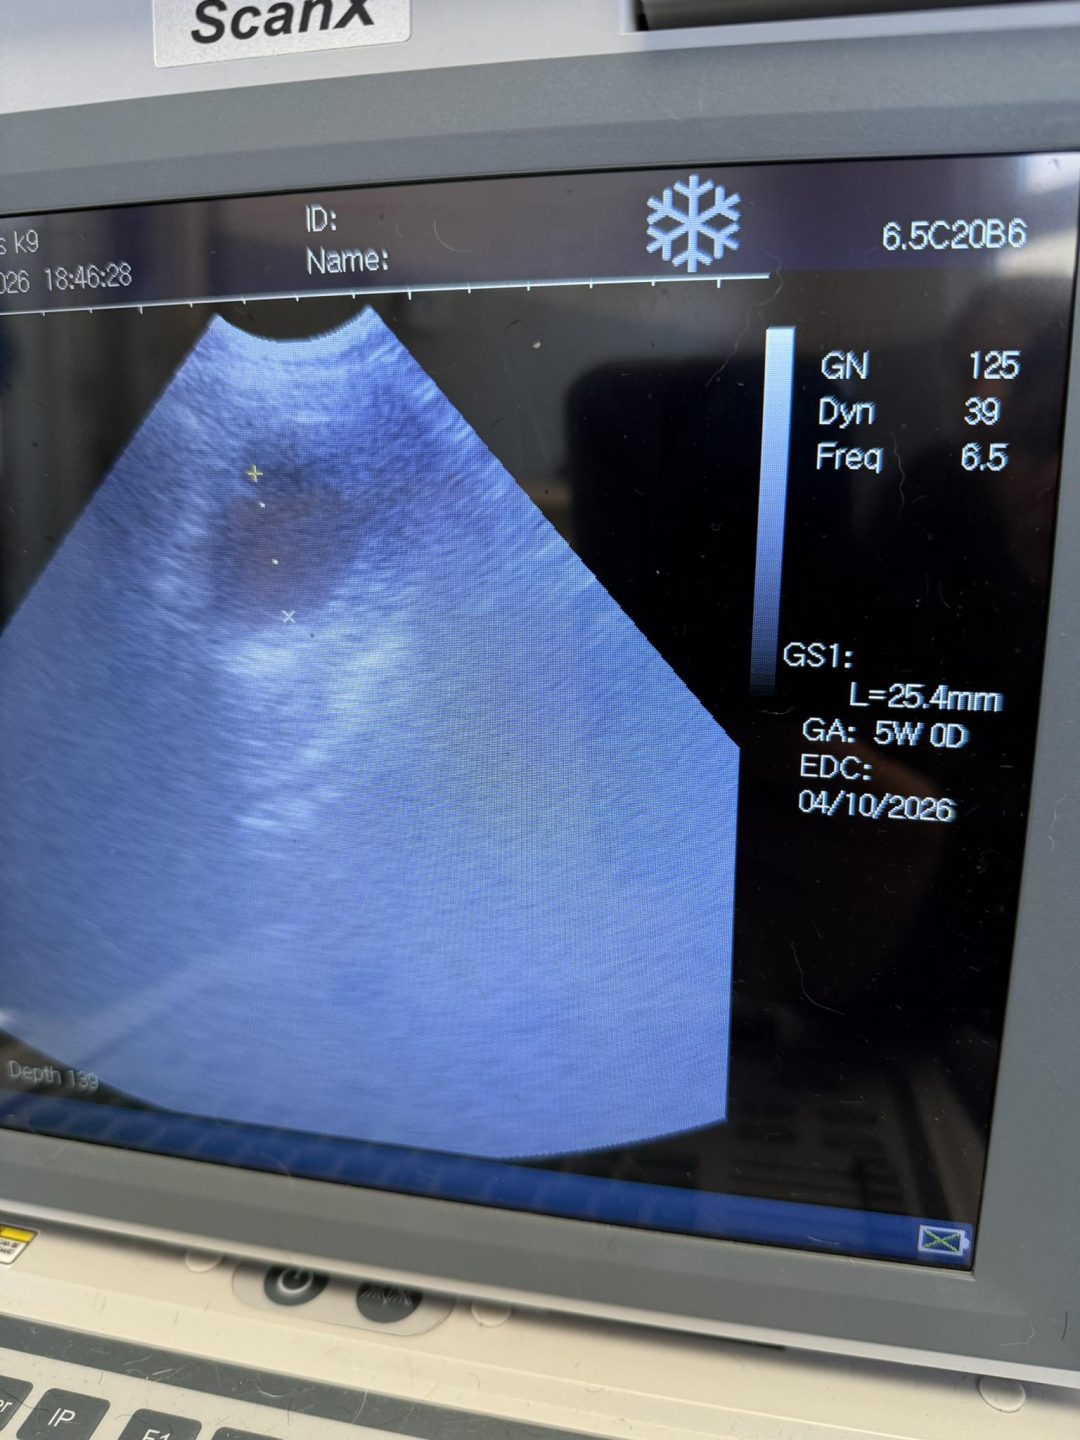

I were called to Presall to carry out two ultrasound scans on two husky girls that had been rescued from a home of 40 dogs

I carried out their scans, taking my time as they were very anxious, and I couldn’t see any babies.

Which is the result we wanted